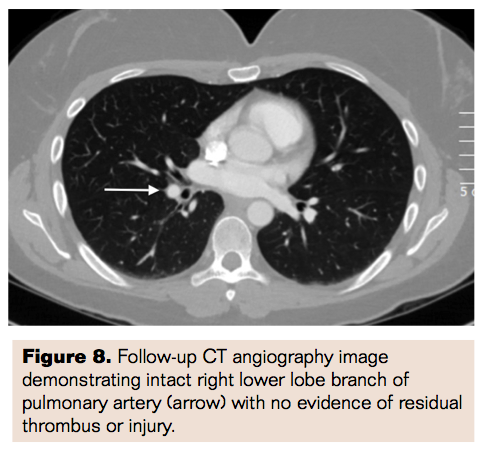

A 37-year-old female with history of multiple deep venous thromboses (DVT) presented with progressively worsening shortness of breath and right leg swelling. Recurrent DVT was attributed to factor V Leiden deficiency and cervical adenocarcinoma, status post temporary inferior vena cava (IVC) filter placement upon initial diagnosis 3 years prior to current presentation and filter removal 6 months later. Right popliteal vein compression was also noted during initial DVT presentation, which was treated with balloon angioplasty and subsequently stent deployment during recurrence 2 years later with a Supera 7 mm x 100 mm self-expanding stent (Abbott). The patient was undergoing comprehensive decongestive therapy and manual lymphatic drainage for 6 months prior to treat her chronic lymphedema from longstanding venous insufficiency. Upon admission, chest x-ray was performed that showed a metallic stent overlying the right lower lobe (Figure 1). Chest CT confirmed pulmonary embolism (PE) with venous stent migration to the right pulmonary artery (PA) (Figure 2).

Access was obtained in the right femoral vein, and iliocaval venogram revealed brisk flow with no evidence of thrombosis and normal caliber iliac veins. A balloon-tipped PA catheter was used to demonstrate elevated right heart pressures with PA mean pressure of 35 mmHg. Angiogram of the PA confirmed the presence of a stent lodged in the right lower lobe branch of the PA (Figure 3). A 7 Fr Pinnacle Destination sheath (Terumo) was then advanced selectively into the right PA, and a 25 mm Gooseneck snare (Covidien) was used to capture the embolized stent edge (Figure 4a). Persistent negative backward pressure on the snare with concurrent positive forward pressure on the sheath was utilized to gradually retrieve the embolized stent into the sheath (Figure 4b) and subsequently externalized from the sheath (Figure 5). Repeat selective PA angiogram revealed persistent clot burden in the right lower lobe branch of the PA (Figure 6). An ultrasound-enhanced thrombolysis catheter (EkoSonic Endovascular System; BTG International) was positioned within the right lower lobe branch of the PA and catheter-directed thrombolysis (CDT) initiated at 1 mg/hr of tPA infusion through the catheter (Figure 7). The thrombolysis catheter was removed after 24 hours and the patient subsequently initiated on anticoagulation with warfarin and discharged home when therapeutic levels had been reached. She was seen in follow-up in 1 month when a repeat CT revealed resolution of the pulmonary embolism (Figure 8) and no residual injury from the embolized stent.